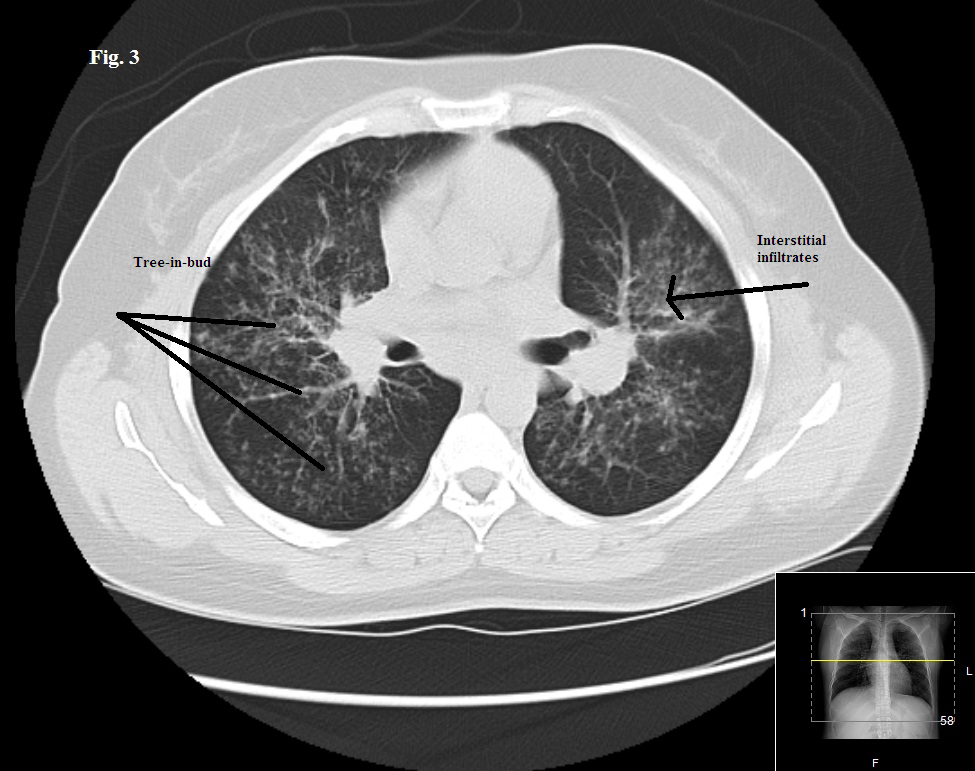

A young woman experienced acute onset of high fever, productive cough, and right-sided pleuritic pain. She was not in sickle cell crisis. Do the images here shed light on cause of symptoms?

Results of a physical examination and CT scan of the chest offer clues to this patient's diagnosis.